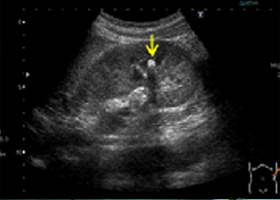

楽天ブックス: 日超検 腹部超音波テキスト第3版 - 日本超音波, 腹部エコー】画像一覧 | 症例・事例 | 矢野医院|射水市の内科,

腹部エコー】画像一覧 | 症例・事例 | 矢野医院|射水市の内科, 腹部超音波検査(腹部US検査、腹部エコー検査)、 血管・体表超,

腹部超音波検査(腹部US検査、腹部エコー検査)、 血管・体表超, 腹部超音波による検査|公益財団法人東京都予防医学協会「元気で腹部超音波テキスト 改訂第三版初心者の方でも分かりやすく書かれています。自宅保管の為、カバーに細かな傷などはありますが、中身は綺麗です。ページの切り取り、破れ、マーカーや書き込みなどはありません。状態は良いと思います。

腹部超音波による検査|公益財団法人東京都予防医学協会「元気で腹部超音波テキスト 改訂第三版初心者の方でも分かりやすく書かれています。自宅保管の為、カバーに細かな傷などはありますが、中身は綺麗です。ページの切り取り、破れ、マーカーや書き込みなどはありません。状態は良いと思います。